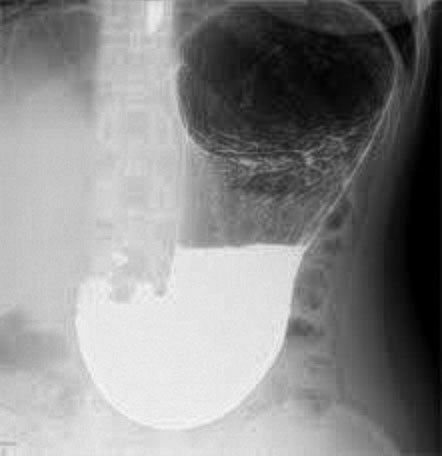

腰椎と大腿骨の写真CT検査 (Computed Tomography/コンピューター断層撮影法)とは、エックス線を使用し、身体の中の様子をコンピューター処理して、輪切りの断層写真を得る検査です。胸部や腹部などのエックス線写真だけでは診断し難いとき、より詳しく精密に検査する方法として用いられます。

CT

右肺腫瘍(肺癌)